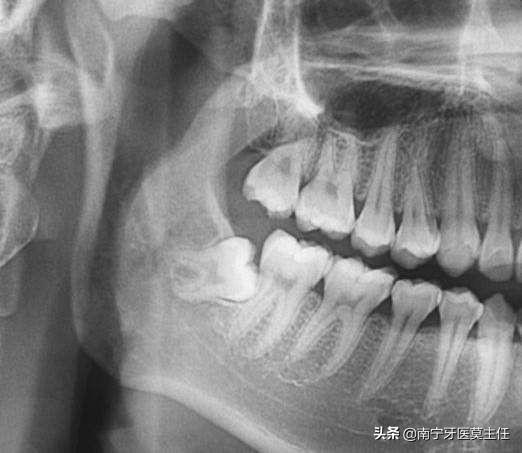

脸部的大小是由颌骨来决定的,而拔掉一个智齿对颌骨的大小没有任何的影响

智齿拔掉以后,充其量对局部的牙槽骨有一定的影响,但不足以改变脸型。